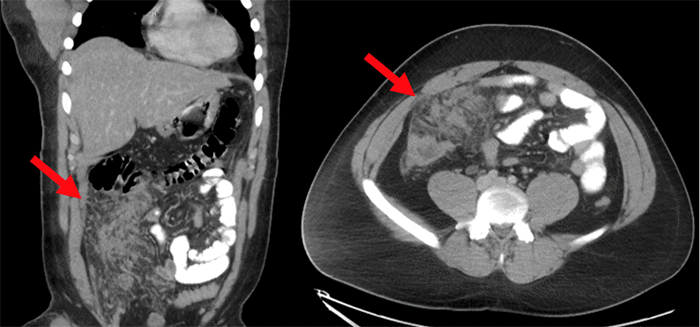

CT imaging demonstrated hepatic steatosis and hepatomegaly (liver span 20.5 cm). The gallbladder, pancreas, spleen, and adrenal glands were unremarkable. However, multifocal abutting soft tissue densities were identified in the central right abdominal peritoneum, extending into the pelvis, measuring approximately 7.5 × 10.4 cm in aggregate. A small amount of pelvic ascites was also present (Figure 1).

Figure 1. Abdominal CT Imaging at Presentation. Published with Permission

Coronal (left) and axial (right) views. Arrows indicate multifocal abutting soft tissue densities within the central right abdominal peritoneum

The symptomatology, physical exam, and imaging initially raised concern for peritoneal carcinomatosis. A review including general surgery, interventional radiology, diagnostic radiology, and internal medicine was conducted. Upon further review, the imaging suggested alternative diagnoses of omental infarction, vascular congestion, or mesenteritis.